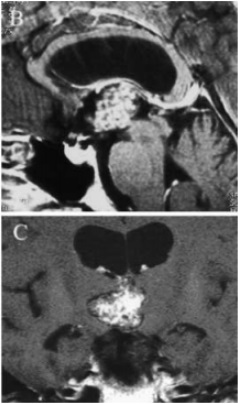

Bella双丘脑海绵状血管瘤导致Monro双孔脑脊液阻塞、颅内压升高。由于由于脑脊液通路在Monro孔、Sylvius导水管受阻,因此需要先放置脑室-腹腔分流术治疗梗阻性脑积水。在随后的手术中,巴特朗菲教授通过经胼胝体入路全切病变,手术成功,无其他任何神经功能缺损。

术后颅脑CT